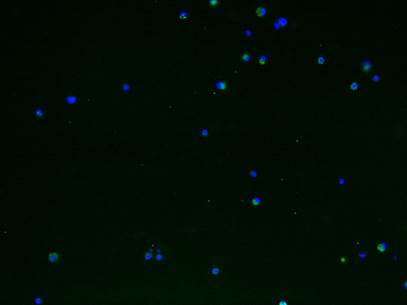

Figure 2

Representative immunofluorescence staining of CCR10, CXCR1, CXCR3 and CXCR5 on the tissular levels of NP, BPH and PCa. CCR10, CXCR1, CXCR3 and CXCR5 are shown by Alexa Fluor 488 (green) and nuclear staining with 4,6-diamidino-2-phenylindole (DAPI; blue). All the pictures are merged from different type of tissues. The Scale bar represents 100 μm.

IF was used to verify the results observed in cell lines at the tissue level. CXCR1, CXCR3 and CXCR5 were either not detectable or were expressed at only low levels in NP tissue. Conversely, they were less or moderately expressed in BPH tissue and highly expressed in PCa. However, CCR10 was either not present or expressed at very low levels in all tissues (Figures 2 and 3).